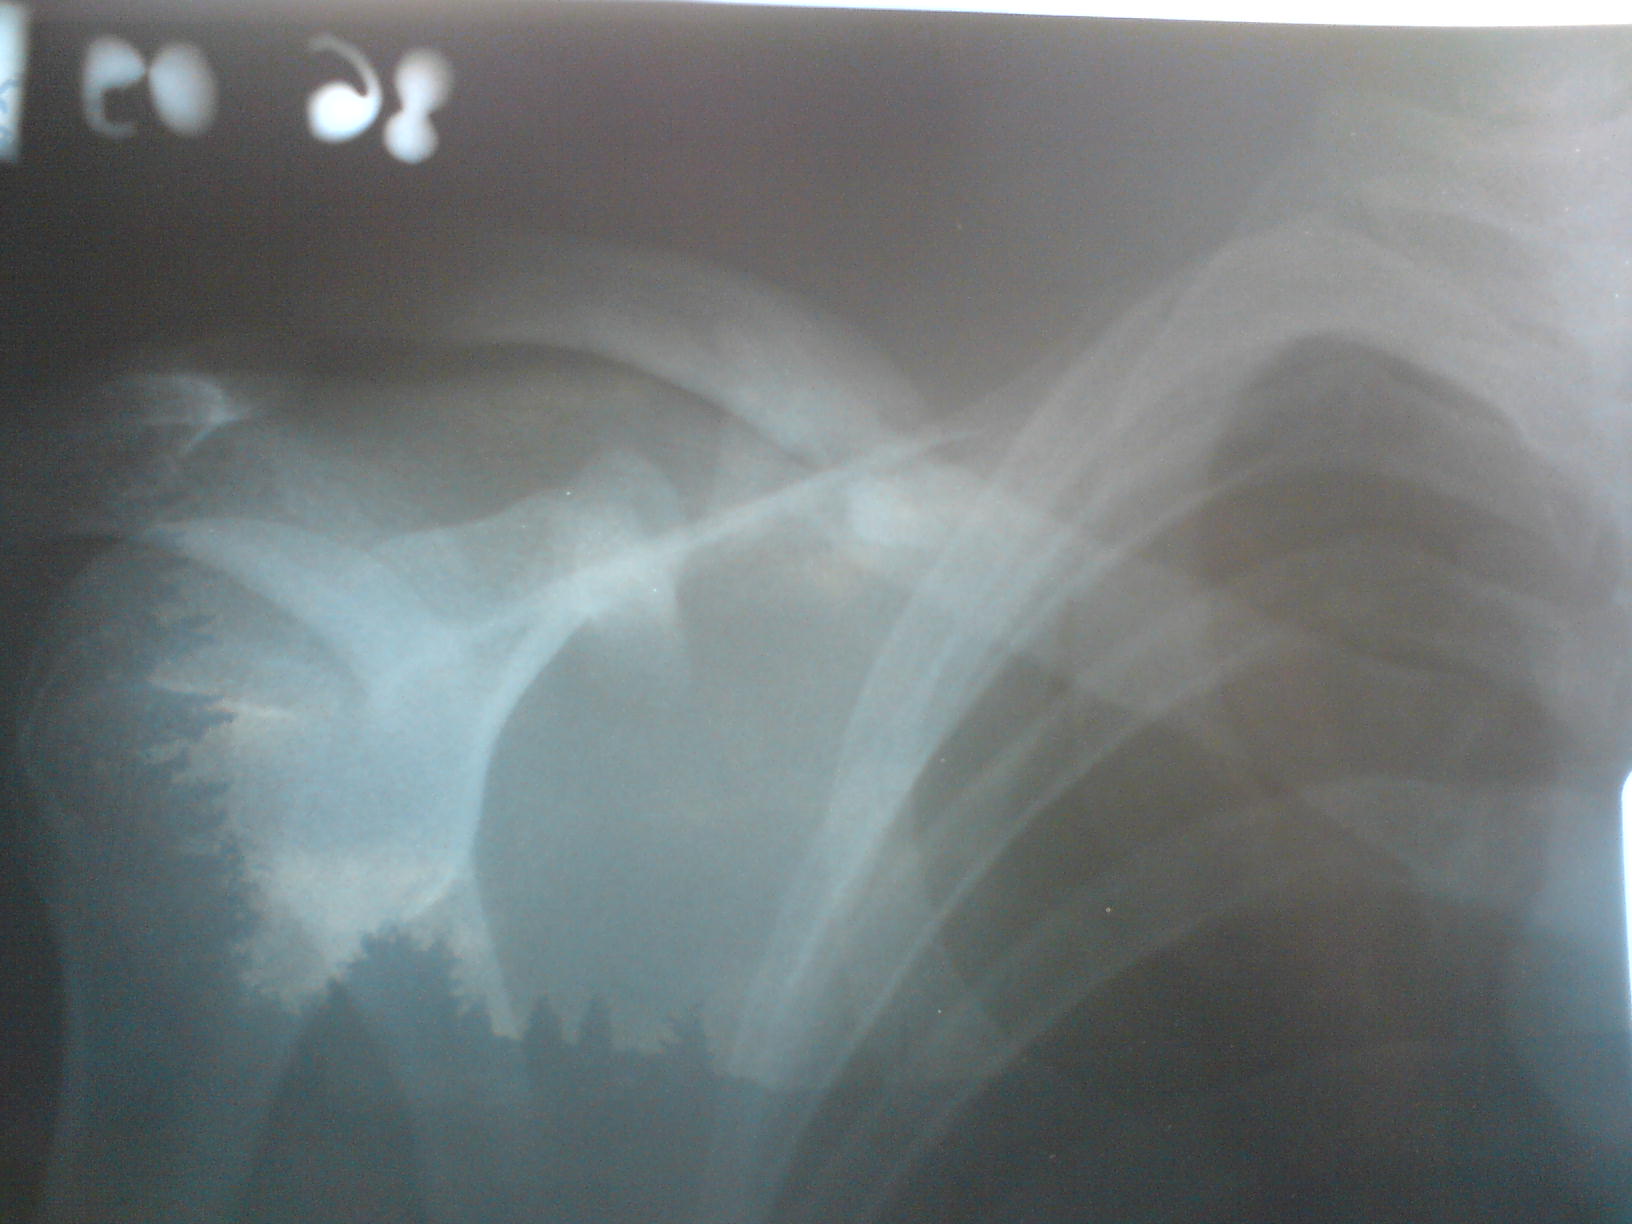

tak takto ro vyzera po tyzdni vraj je to ok a uz mozem aj do prace ... ziadna vyhra heh

mam povoleny aj trenazer ale bez ruk a na biku normalne az najskor o mesiac

Záznam z pohotovosti hovorí niečo ako prominencia claviculy. Nič extra vážne, ale bolí to kvalitne (ľavé rameno).